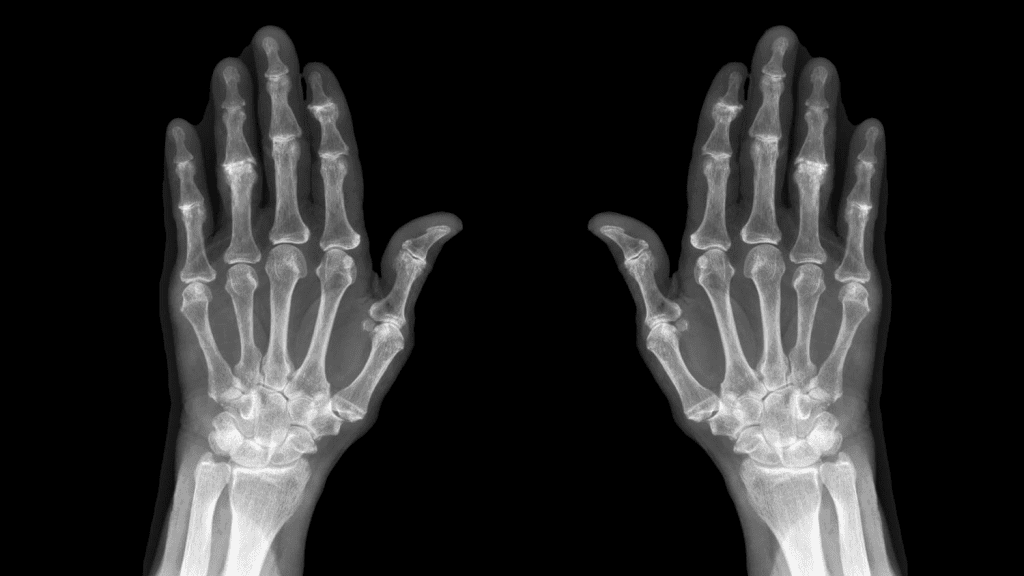

X-Ray Imaging for Osteoarthritis Detection

X-ray imaging is key in spotting osteoarthritis by showing joint damage. It’s a top choice because it clearly shows bone and joint spaces.

How X-Rays Visualize Joint Damage

X-rays are great at showing joint damage from osteoarthritis. They capture images of bones and the spaces between them. This lets doctors see how much damage there is. Joint space narrowing and bone spurs are signs of osteoarthritis seen on X-rays.

Joint Space Narrowing on X-Rays

One key sign of osteoarthritis is joint space narrowing. This can be seen on X-rays. When cartilage wears down, the space between bones gets smaller. X-rays help doctors measure how much narrowing there is, helping with diagnosis and treatment.

Bone Spurs and Osteophyte Detection

Bone spurs, or osteophytes, are abnormal bone growths from osteoarthritis. X-rays can spot these growths, showing how much damage there is. The size and number of bone spurs tell doctors about the osteoarthritis’s stage and severity.

Hand and Finger Joint Imaging

X-rays are often used for hand and finger osteoarthritis. They show joint space narrowing and erosions. Ultrasound can also be used to evaluate joint inflammation and soft tissue changes.